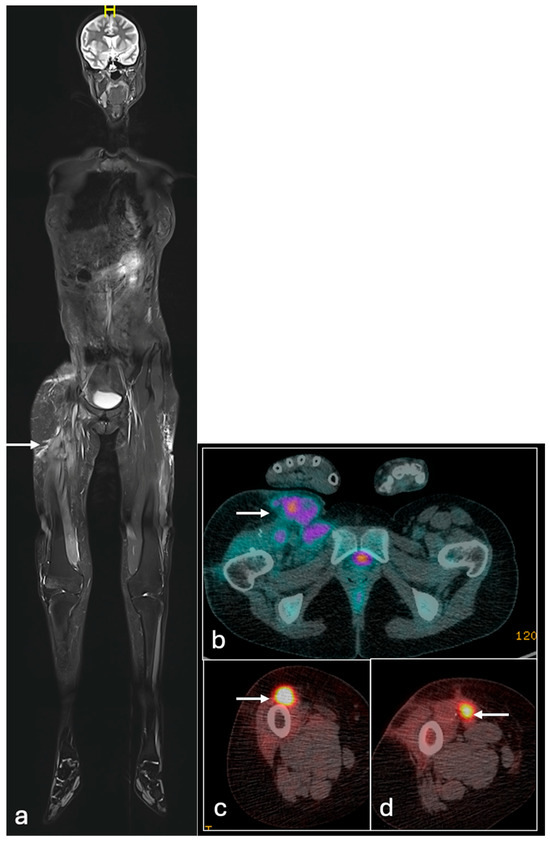

- Plaza de Las Heras, I.; García Cañamaque, L.; Quílez Caballero, E.; Camacho-Arias, M.; Cárdenas Soriano, M.D.P.; Martel Villagrán, J. Positron emission tomography-magnetic resonance imaging applications in pediatric musculoskeletal tumors. Quant. Imaging Med. Surg. 2024, 14, 7825–7838. [Google Scholar] [CrossRef] [PubMed] [PubMed Central]